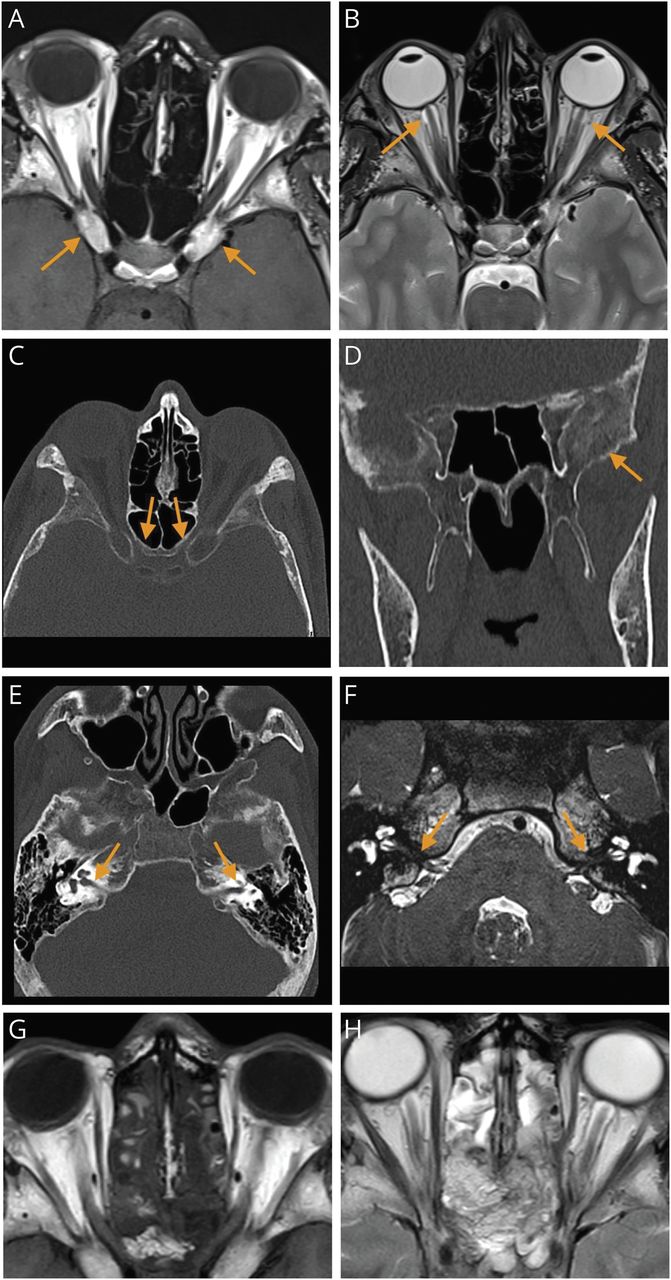

(一)轴向t1加权图像显示前鞍突骨肥大过程与双边视神经管狭窄。(B)轴向t2加权图像显示双边CSF膨胀的视神经鞘拔火罐的视神经头。CSF膨胀只后方延伸视觉运河。(C)轴向CT骨窗显示双边视神经管狭窄。(D)冠状CT重建显示骨骨肥大与“毛玻璃”中央颅底的变化,典型的纤维发育不良。(E)轴向CT扫描显示双边骨骨肥大的坚硬的颞骨内部听觉运河的狭窄。(F)严重核磁共振造影扫描内听道显示双边的第七和第八颅神经的压缩。(G)术后轴t1和t2加权(H)的图像显示双边减压视神经运河持续性脑脊液视神经鞘的膨胀。